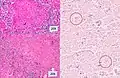

One proposed mechanism is that tuberculous infection in the lungs results in erosion of the epithelial layer of alveolar cells and the spread of infection into a pulmonary vein.[12][13] Once the bacteria reach the left side of the heart and enter the systemic circulation, they may multiply and infect extrapulmonary organs.[13] Once infected, the cell-mediated immune response is activated. The infected sites become surrounded by macrophages, which form granuloma, giving the typical appearance of miliary tuberculosis.[14]

Miliary tuberculosis is a form of tuberculosis that is the result of Mycobacterium tuberculosis travelling to extrapulmonary organs, such as the liver, spleen and kidneys.[11] Although it is well understood that the bacteria spread from the pulmonary system to the lymphatic system and eventually the blood stream, the mechanism by which this occurs is not well understood.[12]